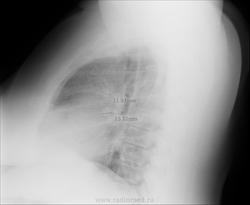

Женщина, 40 лет. Жалобы на длительный кашель.

Снимок мягкий, в легких по мне так чисто. Цепляет правый корень, если есть архив можно посмотреть, какой он был раньше. Если без динамики, то отпустила бы

Сложно судить о патологических изменениях из-за качества рентгенограмм. Возможно, тени, отмеченные Вами на боковом снимке есть и на прямой рентгенограмме ?

Отмеченные на правом боковом снимке тени, думаю, - легочный рисунок, не мтs. Тень, указанная коллегой NIL, вызывает подозрение и желание левого бока.